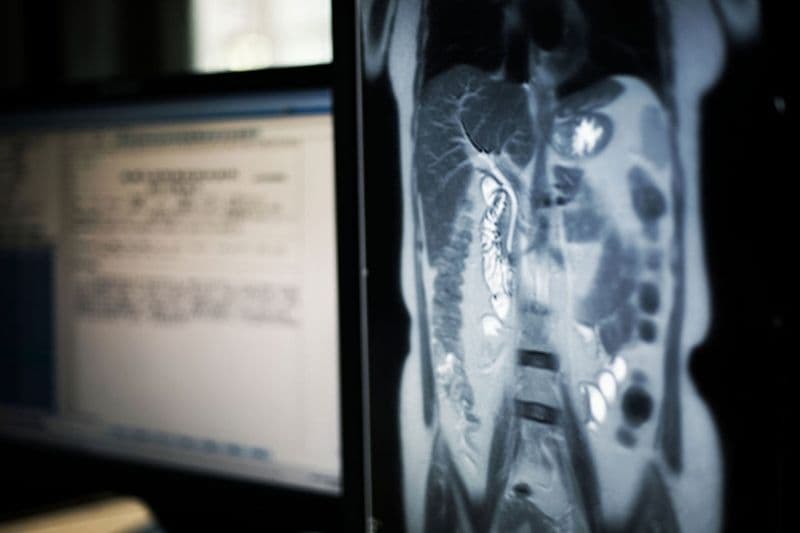

Ung thư đường mật là căn bệnh ác tính phát sinh từ hệ thống ống dẫn mật trong hoặc ngoài gan. Đây là loại ung thư khá hiếm gặp nhưng lại có diễn tiến âm thầm và cực kỳ nguy hiểm. Bài viết này sẽ giúp bạn giải đáp hiện nay phác đồ điều trị ung thư đường mật gồm những phương pháp nào và lựa chọn ra sao theo từng giai đoạn bệnh.

Hiện nay có nhiều cách điều trị bệnh ung thư đường mật khác nhau, bao gồm những phương pháp tiêu chuẩn đang áp dụng và các phương pháp mới đang được nghiên cứu trong các thử nghiệm lâm sàng. Việc lựa chọn phương pháp điều trị phụ thuộc hoàn toàn vào vị trí khối u và mức độ xâm lấn.